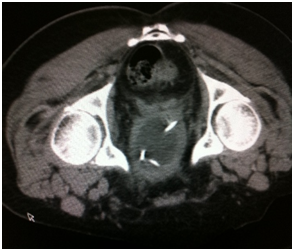

The first and most clinical and cost effective diagnostic tool are urine analysis and ultrasound (Figure 5). CT scan might be used later for further evaluation (Figure 5).

Figure 5 Urothelial cancer in different modalities.